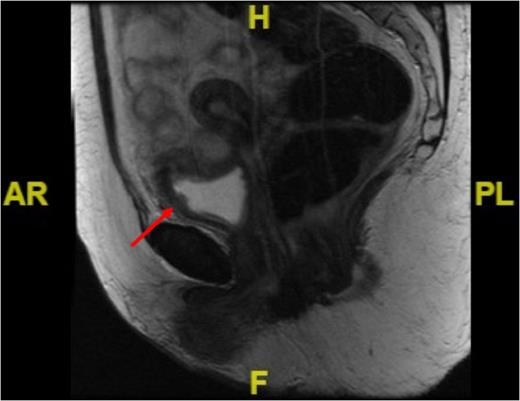

We embarked on close endoscopic surveillance and six weeks later a rigid cystoscopy revealed a 6 cm solid recurrence at the previous resection site. This was completely resected and histopathological analysis again confirmed IMT recurrence with ALK1 gene rearrangement. Due the low reported incidence of metastases bladder conservation was the preferred option but since it recurred so quickly we opted for partial cystectomy. A further pelvic magnetic resonance imaging (MRI) performed 4 weeks post-op demonstrated 22 mm × 10 mm irregular area with associated increased enhancement involving the left anterolateral wall of the bladder which in keeping with the site of the primary resection and no evidence of locally advanced disease (Fig. 3).

Sagittal MRI image of the pelvis showing irregularity in the anterolateral bladder wall at the site of resection (see red arrow).